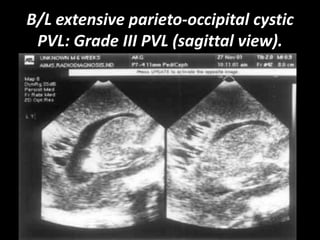

B/L extensive parieto-occipital cystic

PVL: Grade III PVL (sagittal view).

DeVries classification of PVL grading on

ultrasound

• Grade III PVL: Extensive periventricular cystic lesion involving occipital

and fronto-parietal white matter.

B/L extensive parieto-occipitalcystic PVL: Grade III PVL (sagittal view).